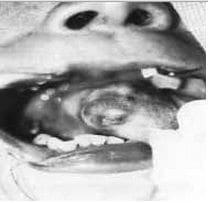

Se presentan macroscópicamente como tumores proliferativos (foto 1) e histológicamente, se caracterizan por presentar una hiperplasia endotelial con o sin lámina vascular y un incremento en el número de células de la matriz durante la fase proliferativa; fibrosis e infiltración grasa, disminución de la celularidad y un recuento normal de la células de la matriz durante la fase involutiva.(foto 2)(1,7)

Foto 1. Hemangioma